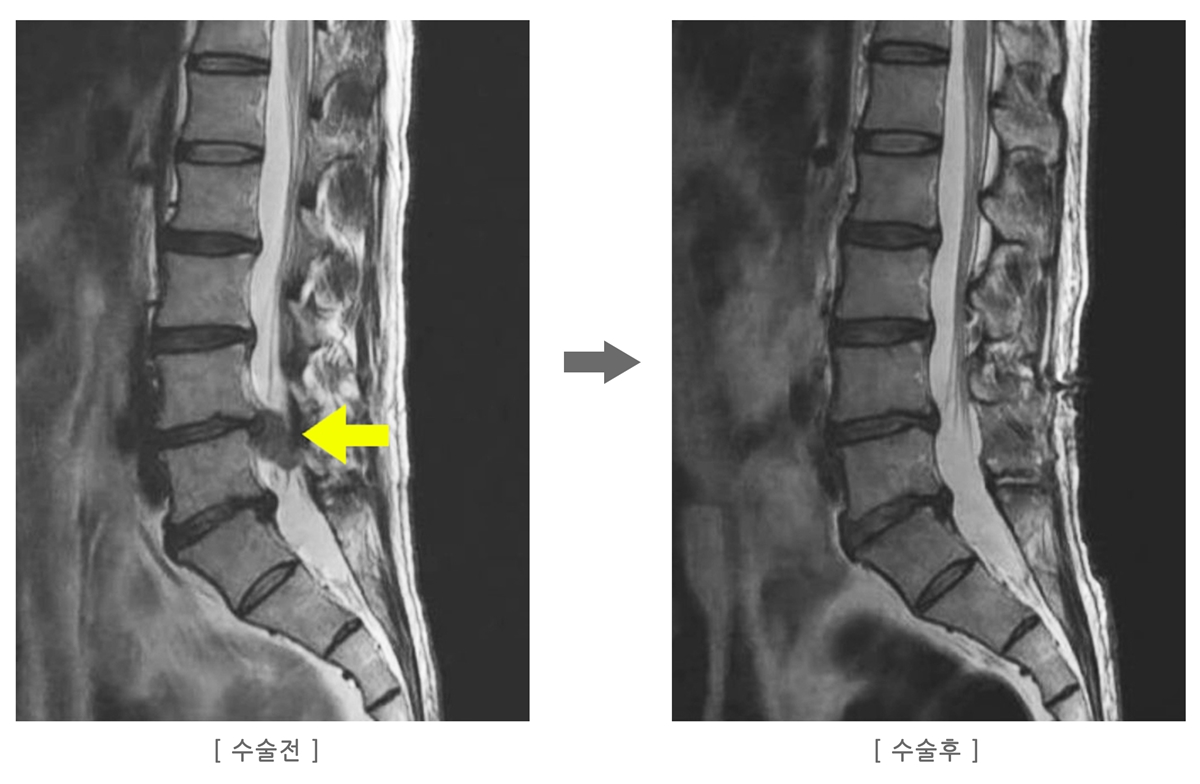

| 허리디스크 수술 전 MRI 판독법 초보자 가이드 (0) | 2025.12.01 |